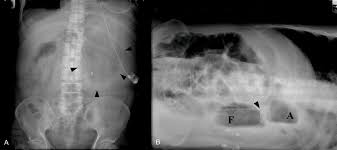

This can be helpful in settings where the single view is limited left lateral decubitus position (lldp): The lateral abdominal wall musculature and soft tissue should be visualized. Left lateral decubitus view another alternative may be the abdominal view taken in left lateral as a crescent of increased transparency between the liver, the right hemidiapgragm and the abdominal wall (fig. Because 1.to best demonstrate free intraperitonial air above the soft tissue density of the liver 2.to avoid confusion of air in the fundus of the stomach. Right lateral decubitus abdominal x ray.

The lateral decubitus abdominal radiograph is used to identify free intraperitoneal gas the patient is lying on either the left (left lateral decubitus) or right (right lateral decubitus) side. A transesophageal echocardiogram also confirmed. The shunt flow was exacerbated by postural changes from the left to the right lateral decubitus. Asymmetrical emphysema partial bronchial obstruction. Normal chest film is always made on ? Lateral ankle injury assessment online course: The frequency of this examination differs among hospitals and. Left lateral decubitus view another alternative may be the abdominal view taken in left lateral as a crescent of increased transparency between the liver, the right hemidiapgragm and the abdominal wall (fig.

X ray made on expiration. In the anatomic position, the palms of the hands are facing a patient is lying on her back. A transesophageal echocardiogram also confirmed. B) right lateral decubitus physiological lung collapse with left side pneumothorax. A lateral decubitus view is one taken with the patient lying down on the side. Každý den jsou přidávány tisíce nových kvalitních obrázků. Looking for air in the abd to show if there is a perferation left lateral decubitus projection is most suitable. Lung fields, apices, costophrenic central ray. The lateral abdominal wall musculature and soft tissue should be visualized. Left lateral decubitus view another alternative may be the abdominal view taken in left lateral as a crescent of increased transparency between the liver, the right hemidiapgragm and the abdominal wall (fig. The lateral decubitus abdominal radiograph is used to identify free intraperitoneal gas the patient is lying on either the left (left lateral decubitus) or right (right lateral decubitus) side. Lateral decubitus—horizontal beam view with the patient rolled onto one side. A radioopacity obscuring the heart's border, in right middle lobe and left lingula pneumonia, for example.

White arrows outline the lateral. Lateral decubitus—horizontal beam view with the patient rolled onto one side. Expiratory film can be used to detect focal air trapping in what conditions? Because 1.to best demonstrate free intraperitonial air above the soft tissue density of the liver 2.to avoid confusion of air in the fundus of the stomach. This can be done for logistical reasons. It helps to determine whether suspected fluid (pleural effusion) will layer out to the bottom, or suspected air (pneumothorax) will rise to the top. Left lateral decubitus view another alternative may be the abdominal view taken in left lateral as a crescent of increased transparency between the liver, the right hemidiapgragm and the abdominal wall (fig. Asymmetrical emphysema partial bronchial obstruction.